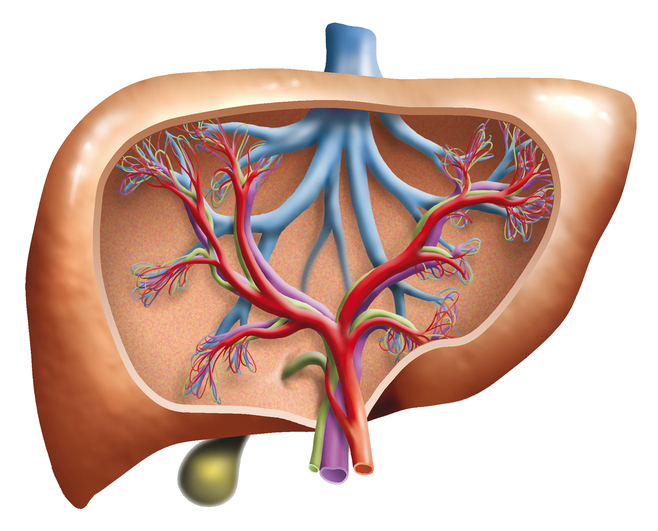

Alcoholism is an ever growing problem faced by societies throughout the world. About 86 percent of Americans over the age of 18 reported drinking at some point in their lifetime. Alcohol Awareness Month, held on April of every year, aims at increasing awareness about its causes, treatment, and recovery. This year the theme is “Changing ...click here to read more